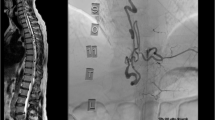

To describe clinical presentations of hereditary hemorrhagic telangiectasia (HHT) patients in Japan. There were 80 patients (40 men and 40 women, age 2–78, mean 39.4 years old), who were either genetically verified or genetically not identifiable but clinically definite HHT patients. Clinical presentations of these HHT patients were analyzed retrospectively. Radiological examinations, which included at least brain magnetic resonance imaging and lung computed tomography, were performed when indicated. Seventy-eight patients had either endoglin (ENG) or activin A receptor type II-like 1 (ACVRL1) mutation. They were 53 HHT1 patients with ENG mutation in 27 families and 25 HHT2 patients with ACVRL1 mutation in 17 families. Two other female patients were clinically definite HHT, but genetic mutation could not be identified. Nosebleeds were noted in 53/53 (100%) HHT1 and 24/25 (96%) HHT2 patients. Telangiectases were observed in 34/53 (64%) HHT1 and 18/25 (72%) HHT2 patients. Pulmonary arteriovenous malformations (AVMs) were noted in 33/52 HHT1 (63%) and 5/25 HHT2 patients (20%). Brain AVMs were detected in 12/51 HHT1 (24%) and 1/25 HHT2 (4%) patients. Hepatic AVMs were noted in 7/29 (24%) HHT1 and 16/20 (80%) HHT2 patients. The number of HHT1 patients was roughly twice as many as that of HHT2 patients in Japan. Pulmonary and brain AVMs were predominantly observed in HHT1 while hepatic AVMs were detected in HHT2. It seemed that ethnicity and regionality had minimal roles in the clinical presentation of HHT.